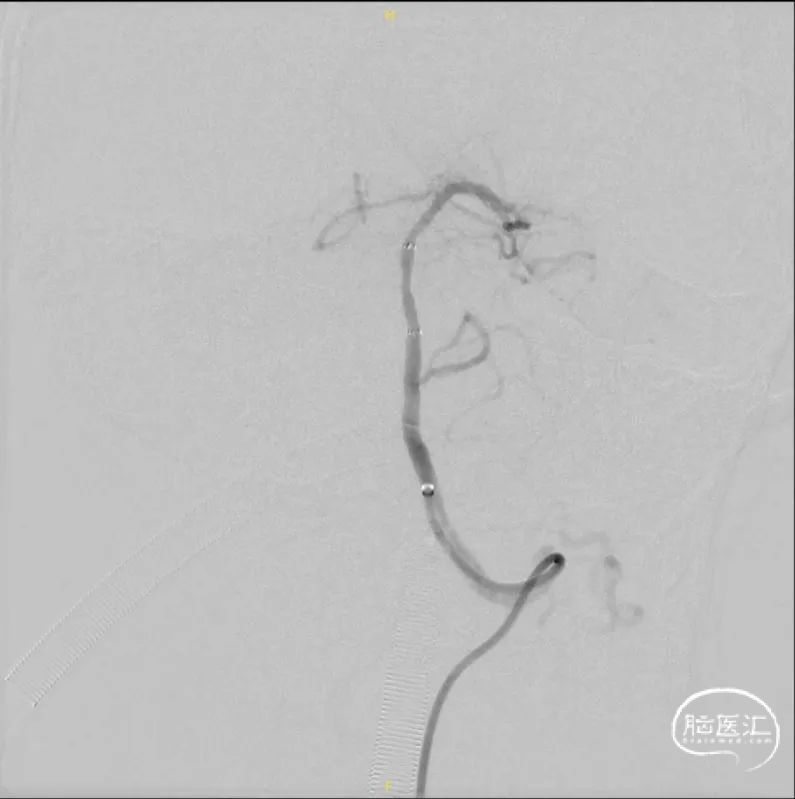

左椎正侧位造影提示:血流缓慢,左椎起始部迂曲,BA下段重度狭窄。

超选左椎行3D旋转造影。

将8F 导引导管置于左侧锁骨下动脉,6F 115cm Navien中间导管置于左侧椎动脉V2段,调整工作角度,于路图下使用HYBRID 1214DA微导丝将SL-10微导管通过基底动脉狭窄段,并置于左侧大脑后动脉。

交换300cm Transend微导丝后,交换1.5*15mm Gateway球囊缓慢扩张。

交换3.0*15mm Wingspan支架,定位准确后释放,交换2.0*9mm Gateway球囊于支架内后扩张。

术后3D旋转造影。